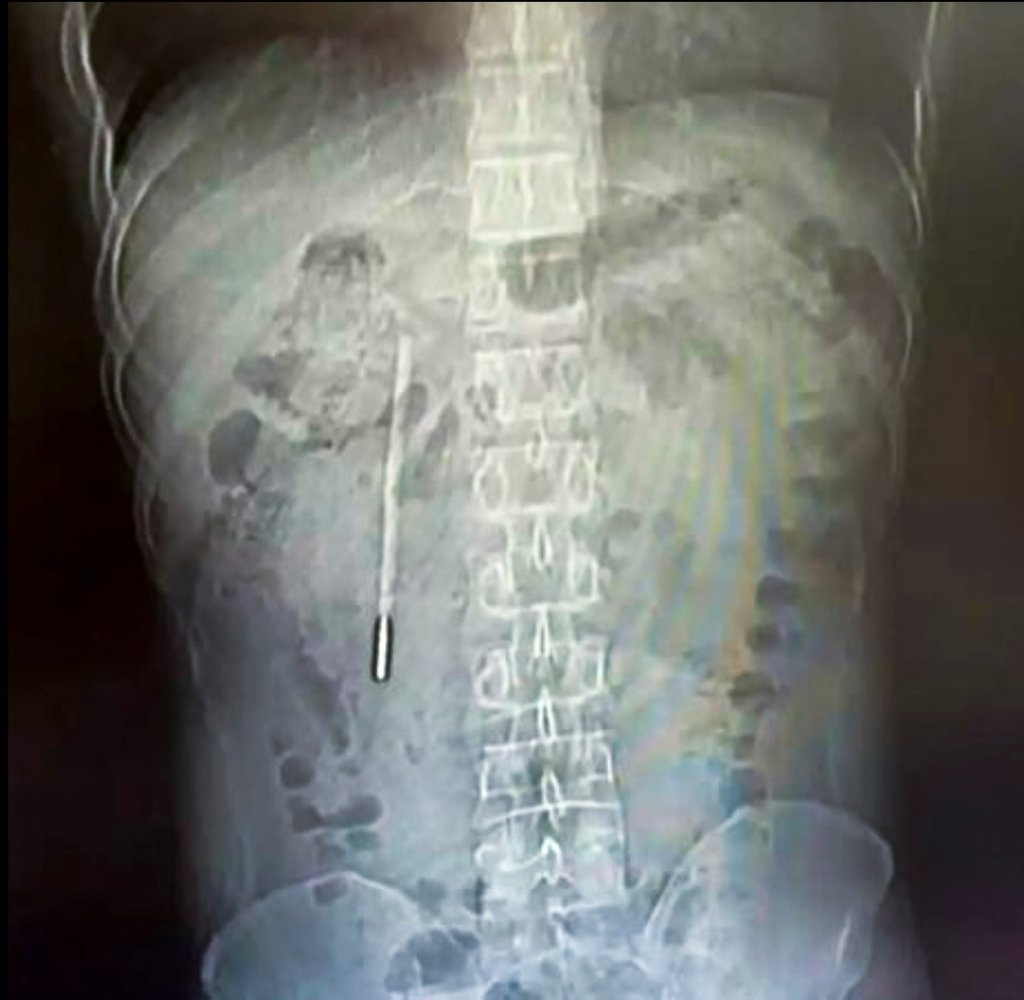

Theo kết quả từ các biện pháp chẩn đoán hình ảnh và chụp chiếu, các bác sĩ chuyên khoa đã phát hiện một dị vật nằm sâu bên trong tá tràng của bệnh nhân. Căn cứ vào hình dáng và đặc điểm trên phim chụp, đội ngũ y tế đã đặt ra nghi ngờ rất lớn rằng vật thể lạ này chính là một chiếc nhiệt kế thủy ngân.

Tình trạng lúc bấy giờ được đánh giá là vô cùng nguy hiểm. Phần đầu nhọn của chiếc nhiệt kế đang trong trạng thái ép trực tiếp vào lớp thành ruột của bệnh nhân. Vị trí và tư thế này đặt ra một nguy cơ cực kỳ cao về việc gây thủng ruột và dẫn đến tình trạng chảy máu trong nghiêm trọng, đe dọa trực tiếp đến tính mạng của người bệnh nếu không được can thiệp kịp thời.

Người đàn ông 32 tuổi họ Vương ở Ôn Châu, Trung Quốc phát hiện nhiệt kế thủy ngân trong tá tràng do vô tình nuốt lúc nhỏ.